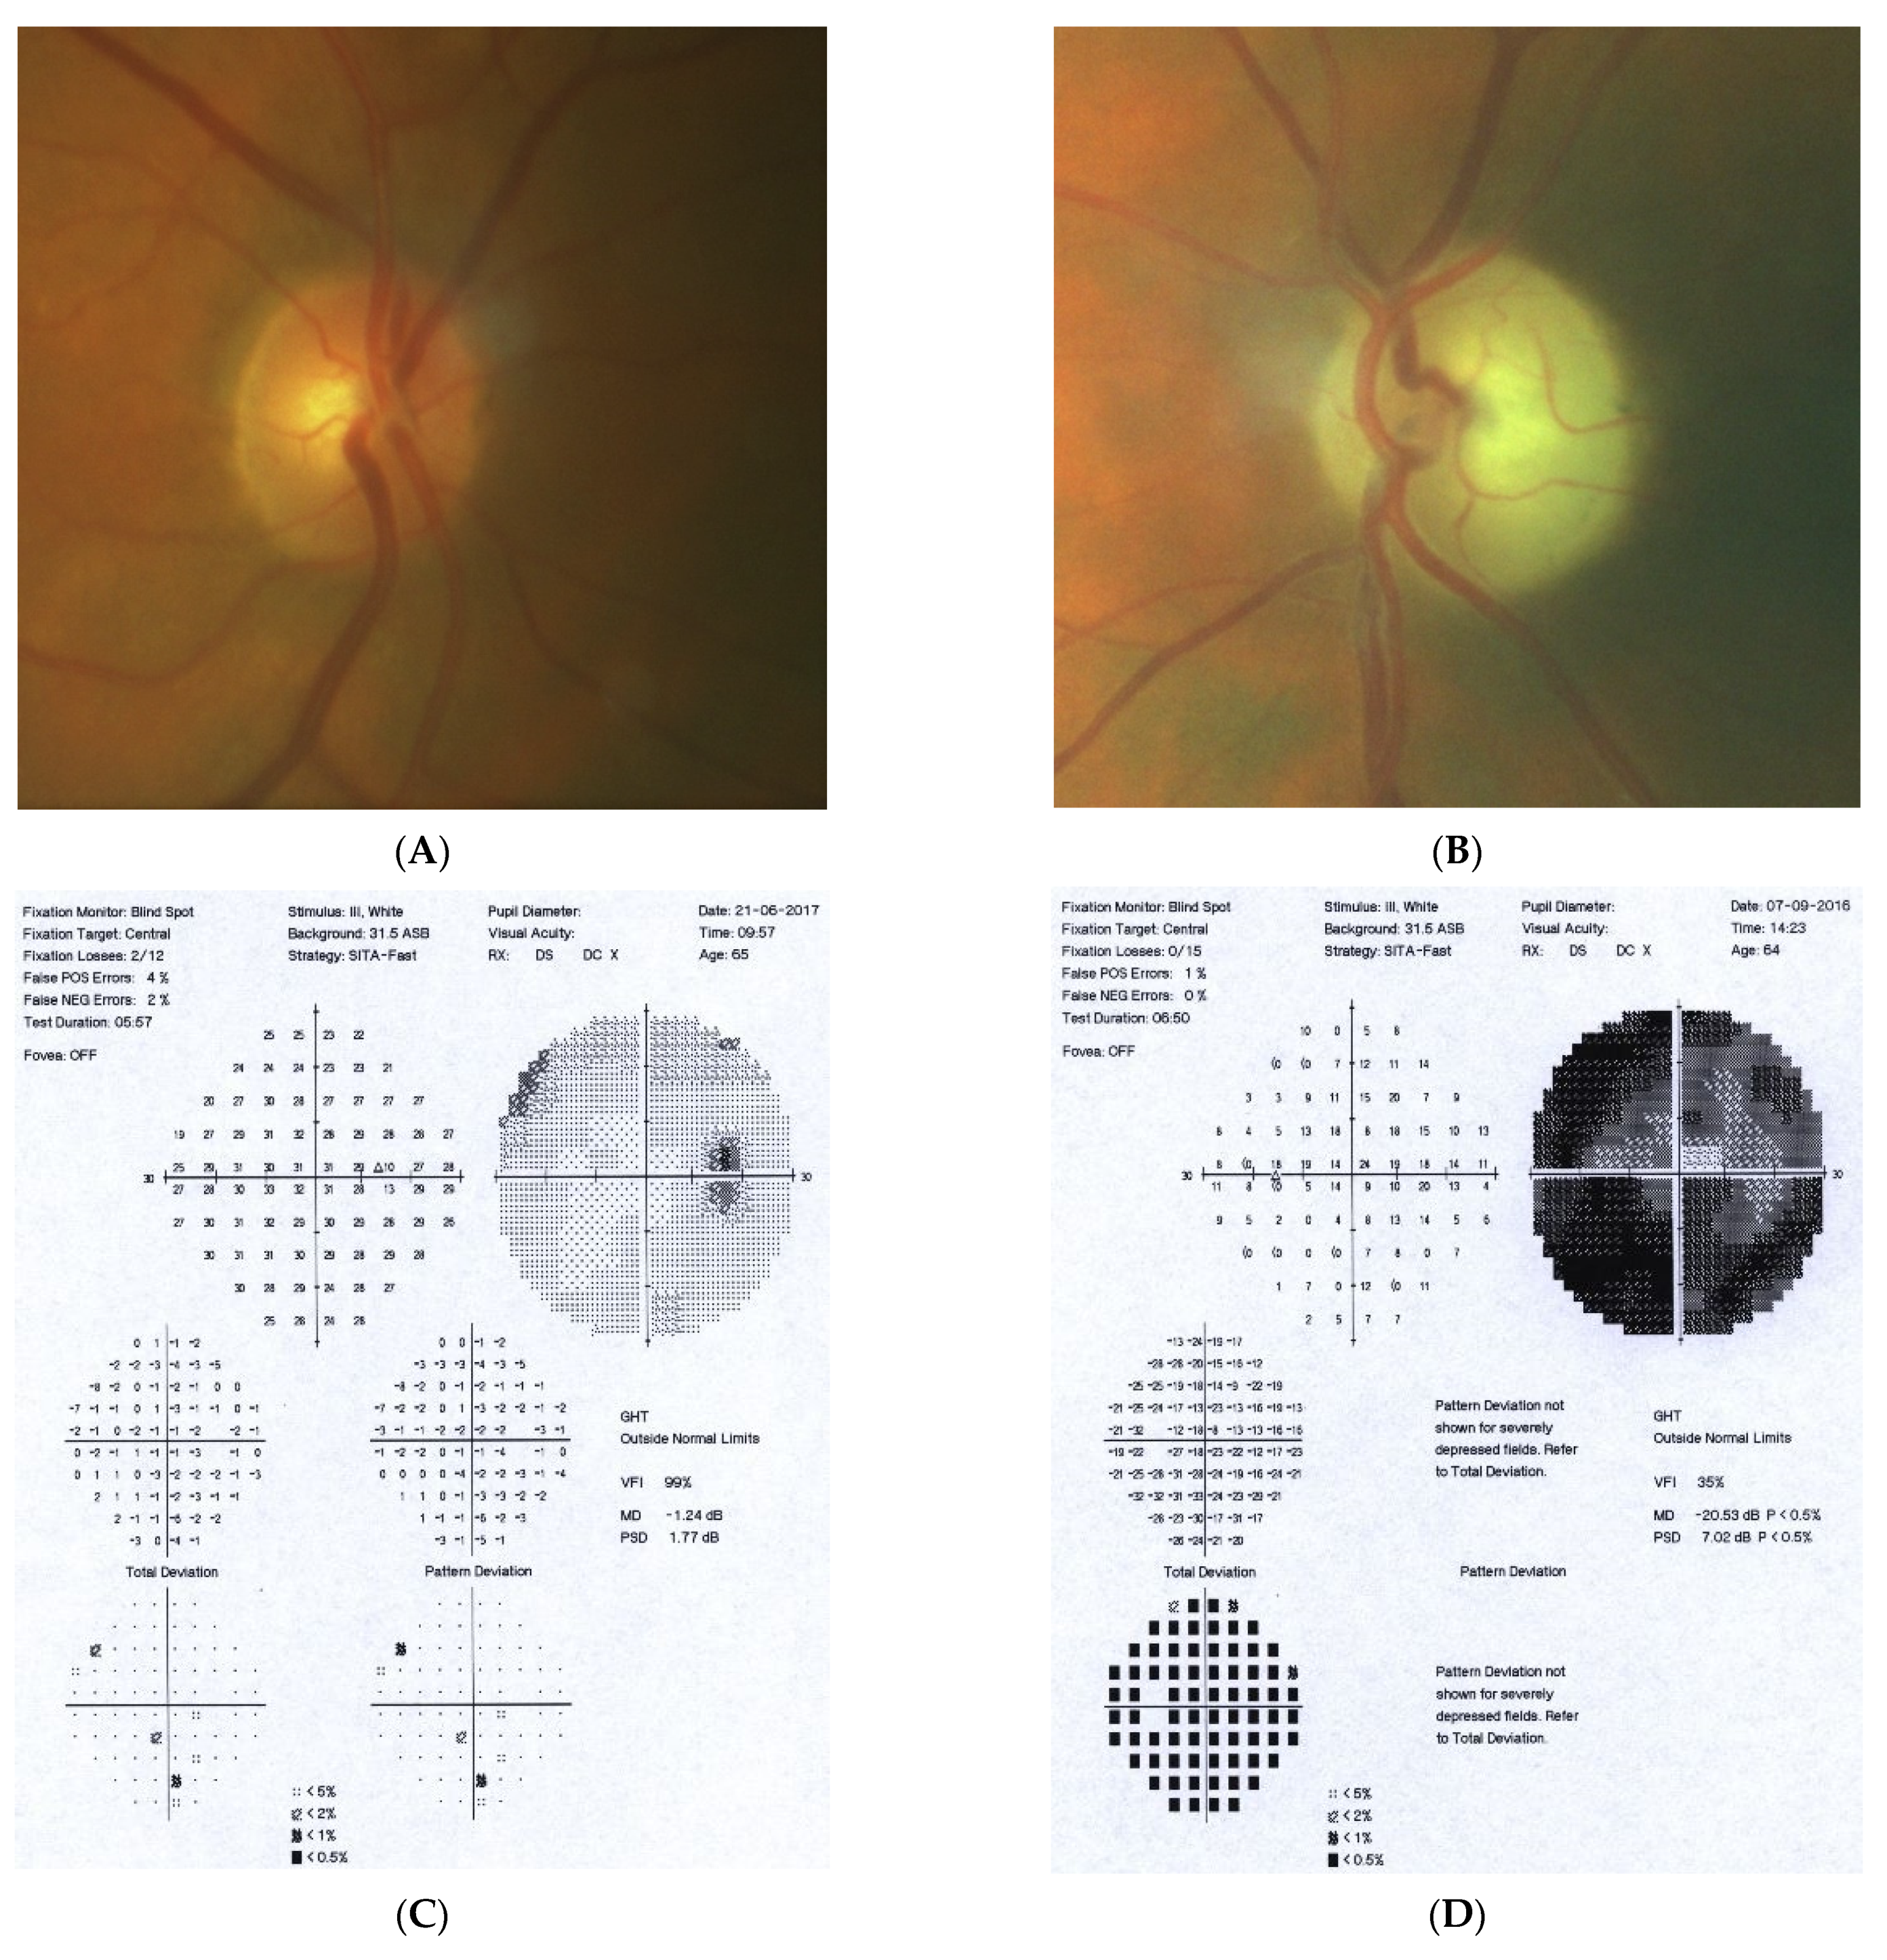

2.2. Case 2

2.3. Case 3

2.4. Case 4